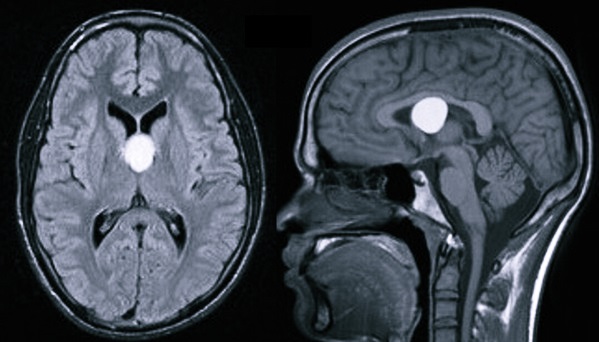

Киста в головном мозге – это объемное доброкачественное образование внутри черепной коробки, которое имеет вид полости, заполненной жидкостью. Нередко оно имеет скрытое субклиническое течение, не сопровождающееся постепенным увеличением габаритов. В основном подозрение на появление кисты внутри головы возникает, если человек страдает эпилептическими пароксизмами либо внутричерепной гипертензией. Одной из особенностей данного заболевания головного мозга является то, что у значительной доли пациентов проявляются симптомы, соответствующие очагу образования кисты – это означает, что для диагностики достаточно всего лишь КТ и МРТ, а также нейросонографии для обследования новорожденного младенца или уже подросшего ребенка.

- Пинеальная киста – шишковидное тело, которое может иметь разные размеры. Ее диагностируют примерно у 1-4% пациентов. Характерным симптомом заболевания является возникновение достаточно сильной головной боли в случае поднятия глаз кверху, но у большинства людей киста не вызывает дискомфорта.

На сегодняшний день основными методами диагностики и последующего прогноза данной болезни являются МРТ (магнитно-резонансная томография) и КТ. Полученная томограмма показывает состояние всех составляющих мозга (эпифиза, мозжечка, гипофиза, нервных ганглий и других частей). С ее помощью можно увидеть место расположения перивентрикулярного глиозного очага и атрофических рубцовых следов внутри головного мозга без вскрытия черепной коробки, оценить их форму, размеры и интраселлярный рост.

Кроме того, данные способы обследования позволяют сделать дифференциальную диагностику промежуточного состояния между доброкачественной кистой и злокачественной опухолью. После внутривенного введения специального контрастного вещества его продукт накапливается в опухолевых тканях, а киста при этом не становится контрастной.